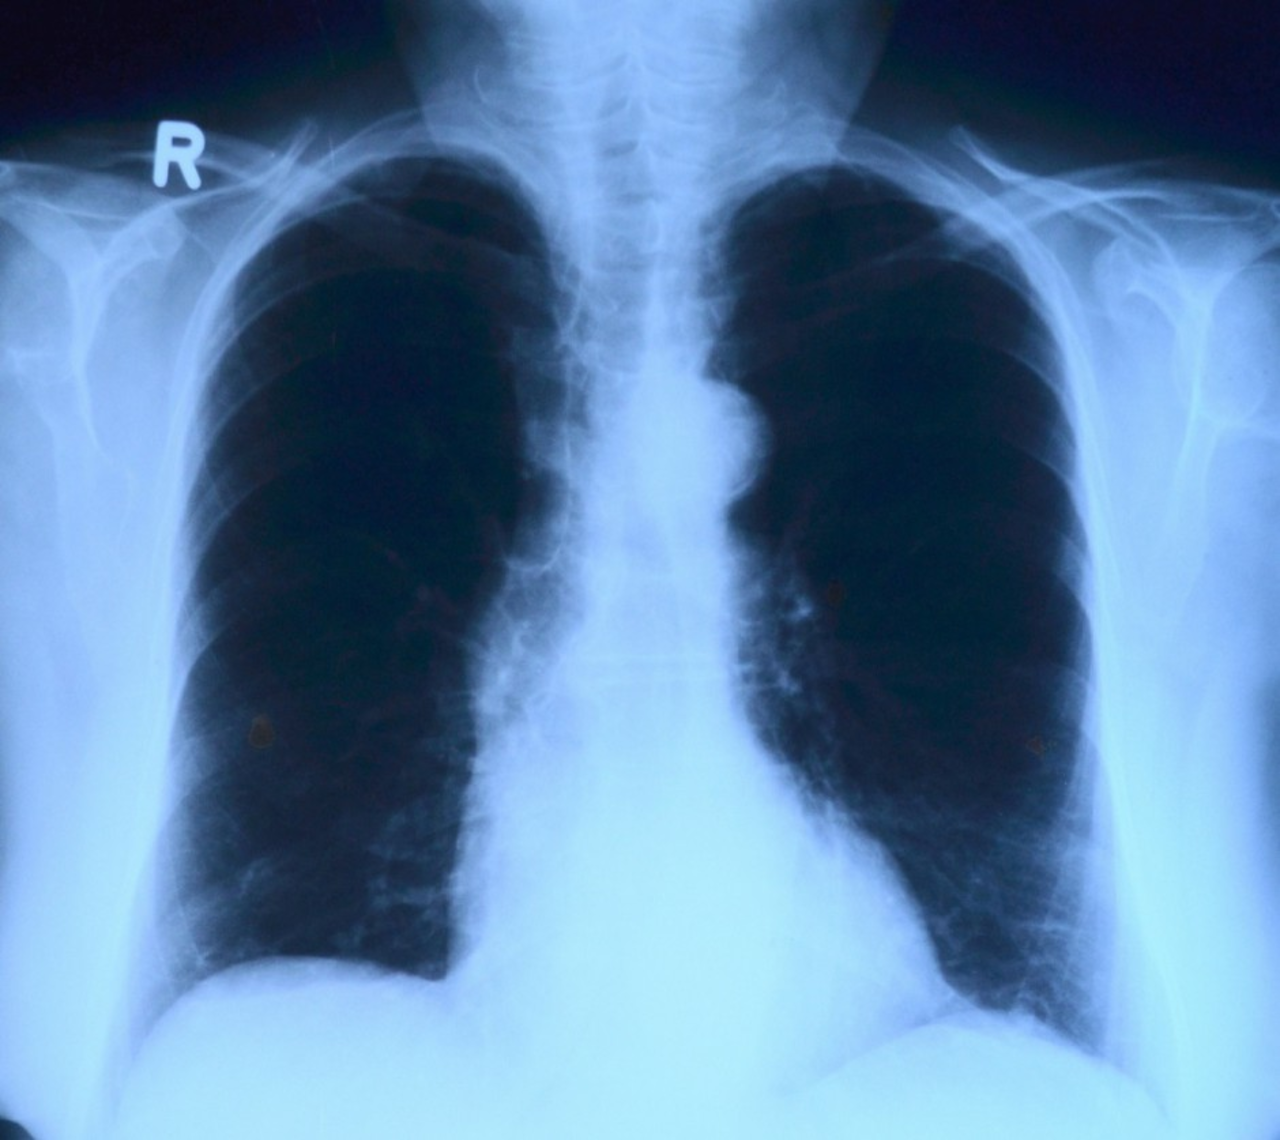

Kolejki do prześwietlenia płuc. Powodem koronawirus

Wzrosła liczba wykonywanych prześwietleń klatki piersiowej, z związku z tym trzeba obecnie dłużej na nie czekać. Wzrost spowodowany jest dużą liczbą pacjentów, którzy wykonują badania po przebytej chorobie Covid-19.

Jak informuje Małgorzata Pawlik, dyrektor przychodni Darimed w Kielcach, w placówce wykonywanych jest blisko 50 procent więcej badań niż przed pandemią koronawirusa. – Stanowczo wzrosła liczba wykonywanych prześwietleń. Czas oczekiwania wydłużył się z jednego dnia do nawet ośmiu dni roboczych.  Na każde prześwietlenie musi być skierowanie wystawione przez lekarza POZ bądź z prywatnej przychodni  - dodaje dyrektor.

Jak podkreśla dr Zbigniew Bajor, pulmonolog, osoby które przeszły Covid-19, a czują następstwa ze strony układu oddechowego, powinny wykonać prześwietlenie płuc. – Gdy po przebytej chorobie nadal występuje kaszel, duszności czy spadek wydolności oddechowej, a dodatkowo widoczny jest spadek saturacji, wskazane jest takie badanie. W przypadku wystąpienia zmian w płucach, które łączą się z występującymi objawami, może to wymagać pogłębionej diagnostyki  w postaci tomografu komputerowego – tłumaczy specjalista. – Warto się jednak skonsultować ze specjalistą, który oceni, na ile jest to konieczne – dodaje lekarz.

Zdaniem lekarzy, okres rekonwalescencji po przejściu Covid-19 zależy w dużym stopniu od przebiegu infekcji i od stanu zdrowia pacjenta. W niektórych przypadkach może trwać nawet kilka miesięcy, np. u osób chorujących na astmę.